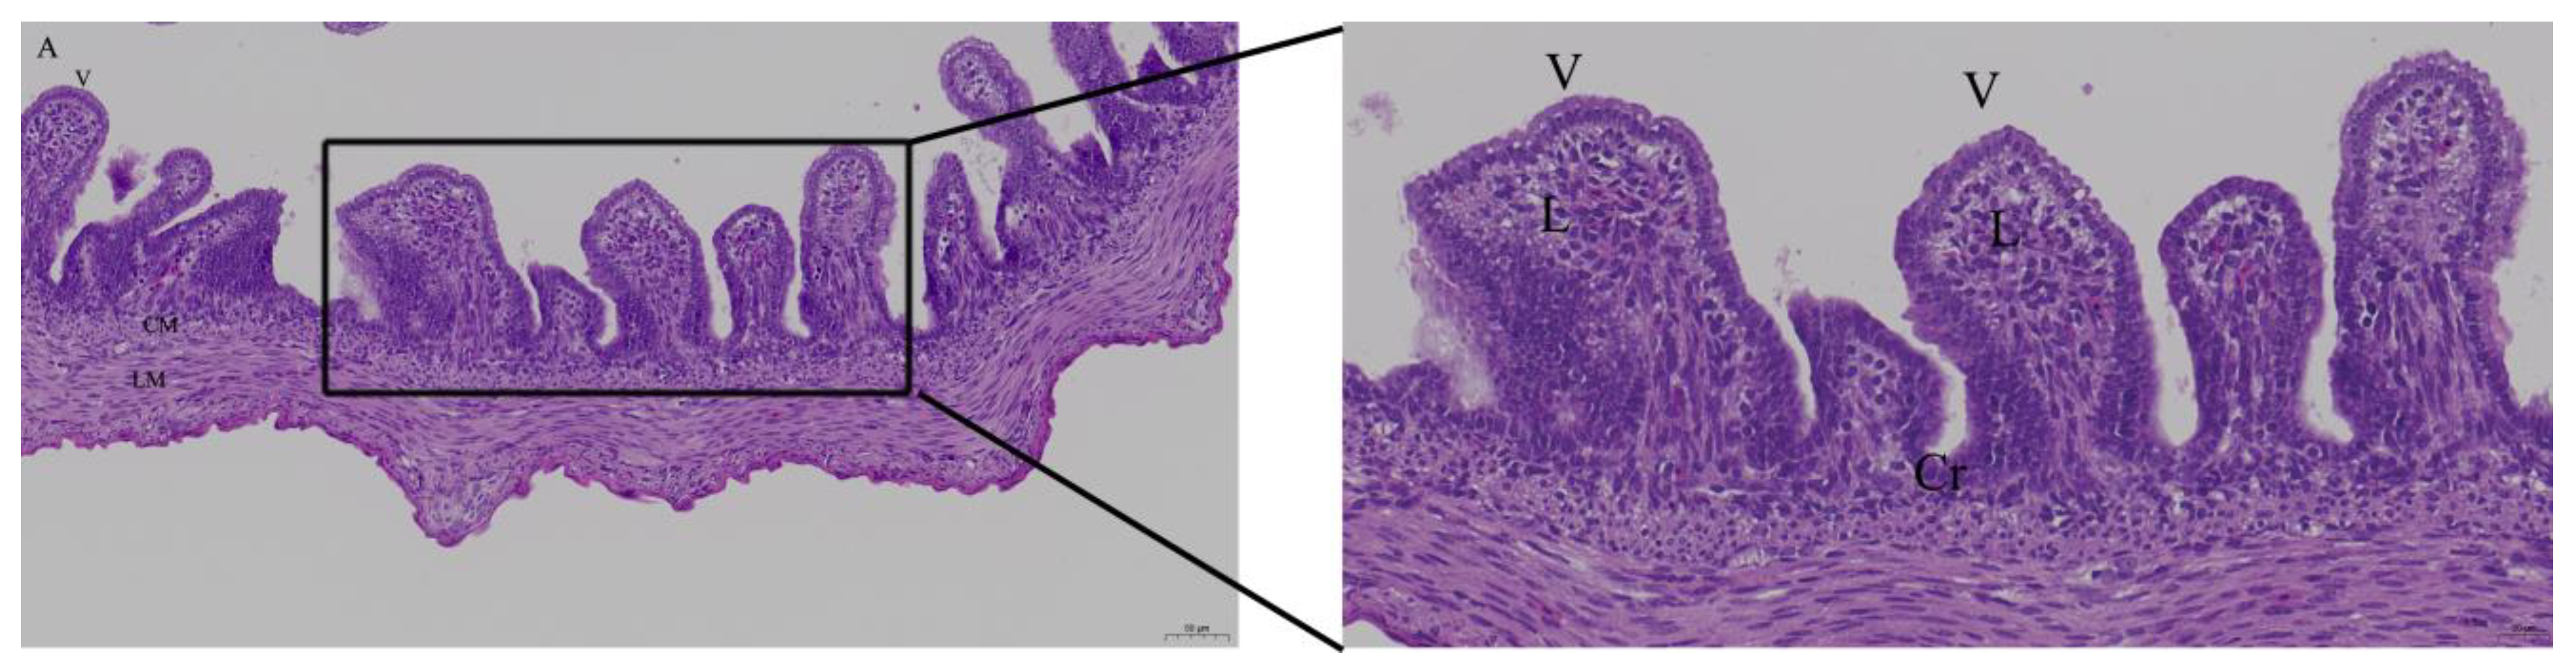

When the LPS dose was 125ng, there was bleeding in lamina propria of intestinal epithelial cells; there was inflammatory cell infiltration in the Peyer’s patch in LPS group. In quercetin group, intestinal epithelial cells had no inflammatory cells infiltration. (Figure 3).

Figure 3. Histopathologic changes of the duodenum induced by LPS and treated with quercetin, with 40 nmol/egg in chicken embryos. Fifteen day-old embryonated eggs were inoculated with LPS (125 ng/egg) and quercetin (Q) at 40 nmol/egg by injection into the allantoic cavity. The duodenum was histologically examined on day 19 (4 days after treatment). Hematoxylin and eosin staining. (A) Control group; (B) There were inflammatory cell infiltration in the Peyer’s patch in LPS group (arrow); (C) Treatment group (125ng LPS/egg + 40 nmol quercetin/egg). The right photo was the rectangle of the left one magnified by 2 folds. Scale bar of left photo (200×): 50 μm. Scale bar of right photo (400×): 20 μm. V: villus; Cr: crypt; P: Peyer’s patch; L: lamina propria; CM: muscularis externa, inner circular; LM: muscularis externa, outer longitudinal.

The intestinal mucosal barrier function is the first line of defense against pathogens, nutritional deficiency, and stress. The elements of mucosal barrier function have four parts: epithelia, mucus layer, mucosal immune system, and microbiota. Mucosal barrier function depends largely on dynamic balance of epithelia cell proliferation, differentiation, migration, apoptosis, and shedding. The renewal process of intestinal epithelia lasts approximately one week. Chicken embryos start to ingest the amniotic fluid around 17 days of incubation, stimulating the rapid development of intestinal mucosa [15]. In our intestinal inflammation model, we injected LPS and/or quercetin into the allantoic cavity at 15 days of incubation just before the ingestion of amniotic fluid. LPS induced duodenal mucosa inflammation structurally characterized by inflammatory cell infiltration into the Peyer’s patches in the LPS group. Quercetin enhanced the inflammatory response compared to the untreated control group. This suggests that quercetin may improve intestinal health and could be used as a digestive aid or alternative medicine to treat diarrhea.